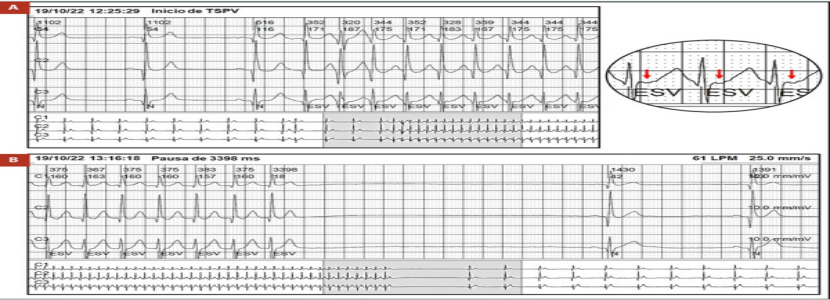

动态心电图结果显示:患者存在数次阵发性室上性心动过速发作,且在心动过速终止后出现长达3.4s的长RR间期(图1A、1B),发作时患者伴随头晕及晕厥前兆,提示心动过速后的长间歇可能是晕厥的直接诱因。结合症状与检查结果,门诊医师再次建议住院评估病情及是否需行起搏器置入术。

((图1A,阵发性室上性心动过速发作,RR规则,频率为170次/分,PR间期大于90ms,红色箭头表示逆行P波。图1B PST发作后窦停3.4s))